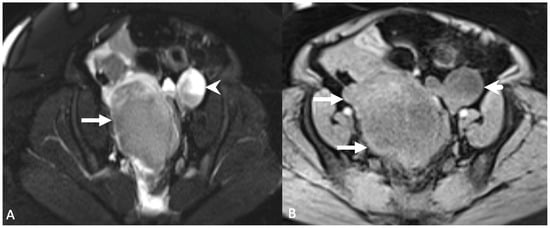

5.1.5. Paraovarian Cyst

5.1.6. Peritoneal Inclusion Cyst